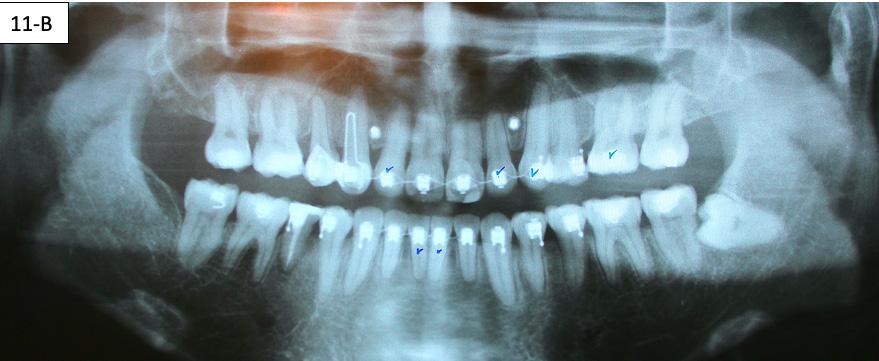

Panoramic radiogram revealed complete permanent dentition with mandibular left impacted wisdom tooth. Roots of the mandibular second bicuspids appeared to be short. There was an excellent bone support and no sign of periodontal or periapical pathology. (Figure 5-B).

11B: Pre-de-bracketing, panoramic radiogram